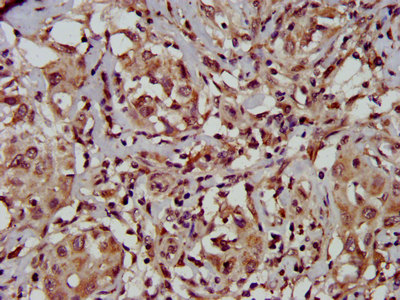

IHC image of CSB-PA023420LA01HU diluted at 1:500 and staining in paraffin-embedded human liver cancer performed on a Leica BondTM system. After dewaxing and hydration, antigen retrieval was mediated by high pressure in a citrate buffer (pH 6.0). Section was blocked with 10% normal goat serum 30min at RT. Then primary antibody (1% BSA) was incubated at 4°C overnight. The primary is detected by a biotinylated secondary antibody and visualized using an HRP conjugated SP system.